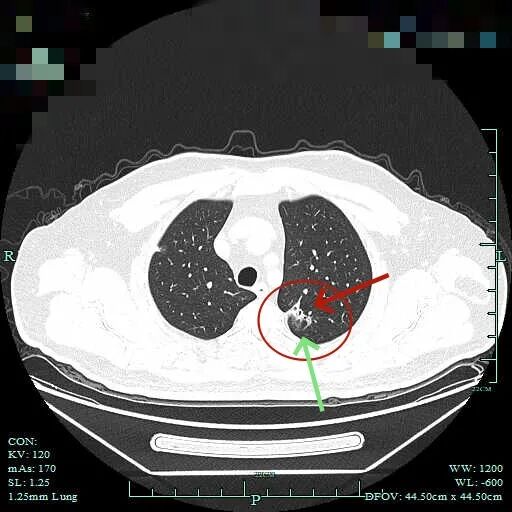

杭州市肿瘤医院影像展示与分析:

右上也有混合密度结节,实性部分缺乏膨胀性与收缩力,磨玻璃成分较淡,也偏糊,但持续存在仍得考虑肿瘤范畴可能性大。

此视角是混合密度,实性为主,贴胸膜近。